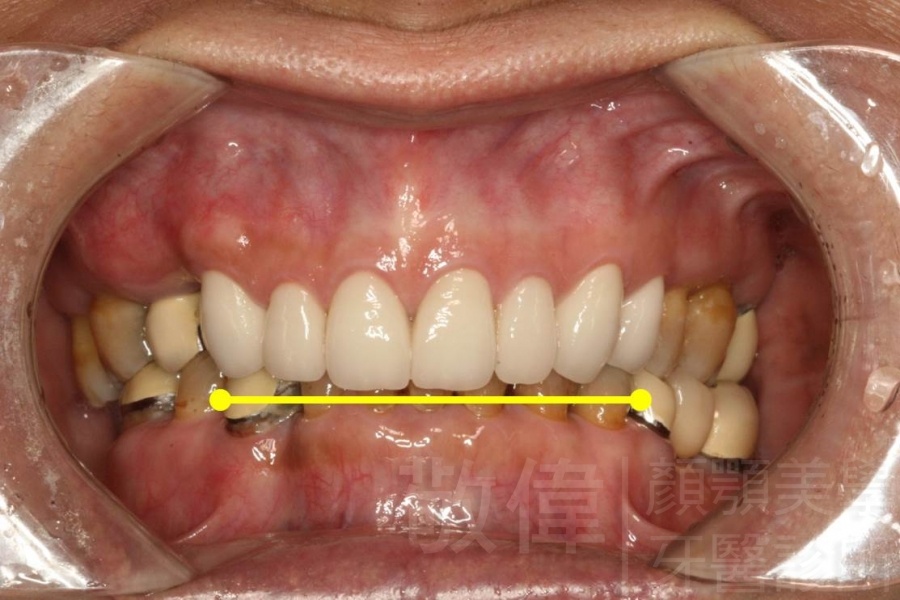

| 6 | 前牙美容 | 矯正+牙齦增補+晶鑽全瓷冠 | ||

| 7 | 前牙美容 | 矯正+晶鑽全瓷冠 | ||

| 8 | 前牙美容 | 快速矯正之美容晶瓷貼片及晶鑽瓷冠 | ||